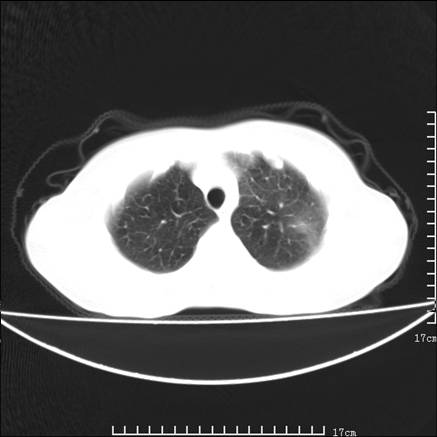

女,46岁,患胃溃疡多年,溃疡大小约1.0cm左右,后于5年前手术,病理为胃癌。主诉:半月前感冒后胸闷,气短,有咳嗽,无明显咳痰,无发热。偶有腰背部不适。

以下为高分辨扫描图像

双肺小叶间增厚,双肺散布粟米影和磨玻璃状影,以双肺上叶为重。结合病史考虑转移(癌性淋巴细管炎)可能性大。

结合病史:认为是典型肺部癌性淋巴管炎、淋巴结转移。请看图解。

正如caihe主任所言,影像表现结合临床病史应该支持肺癌性淋巴管炎;上肺大片边缘不清的渗出病变,多系感染所致,临床有感冒病史并咳嗽表现。肺癌性淋巴管炎临床一般无咳嗽、咳痰症状。

肺癌性淋巴管炎征象分为主要征象及合并征象,主要征象包括:

1、近肺门支气管血管周围间质结节状增厚;

2、小叶间隔结节状增厚;

3、小叶中央间质结节状增厚;

4、胸膜下间质结节状增厚。

合并征象为:纵隔淋巴结增大,胸腔积液,肺多发随机分布的小结节等。